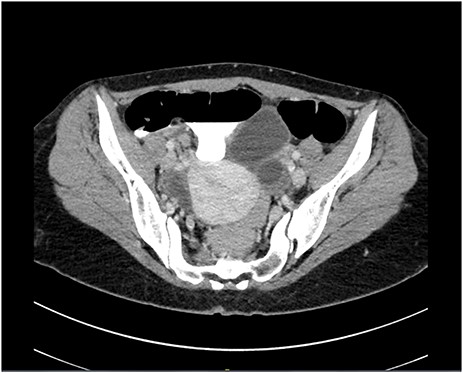

A pelvic ultrasound was normal. Gynecological causes of pain were ruled out. A computed tomography (CT) scan of the abdomen and pelvis demonstrated acute noncomplicated appendicitis (Fig. 1). WBC count was 9.42 x109/l with a neutrophil differential of 62.3%. The general surgery service was consulted for the findings. After a full history, physical examination and review of laboratory results and imaging, the patient was taken to laparoscopic appendectomy on the same day of presentation.

Computed tomography scan in a transverse cut demonstrating an inflamed appendix